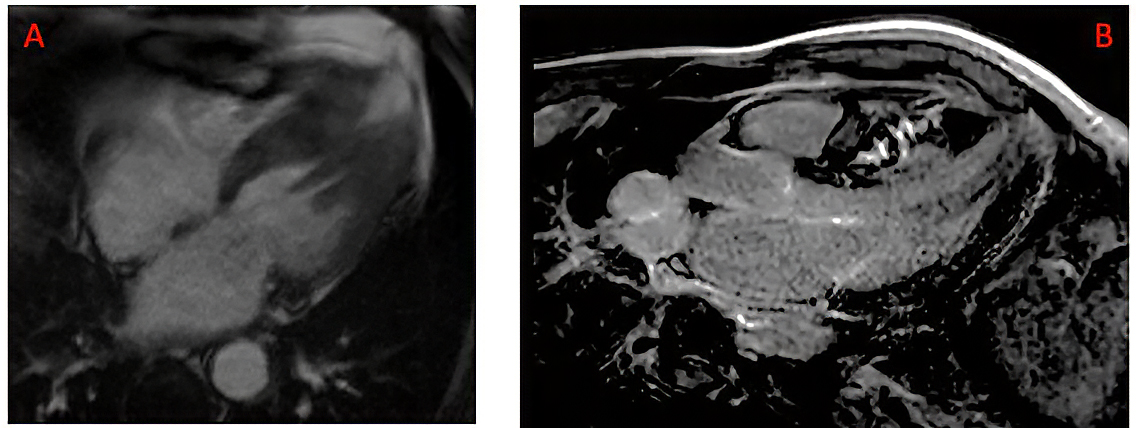

Figure 2. CMR examples of apical aneurysm and late gadolinium enhancement.

A) Ciné long axis 4 chamber view in end-systole showing the presence of an apical aneurysm; (B) Late gadolinium enhancement of mid-wall distribution located in the interventricular septum. CMR: cardiovascular magnetic resonance

Left ventricular apical aneurysms are detected in approximately three to five percent of patients when systematically assessed by cardiovascular magnetic resonance. They are characterised by thin-walled, akinetic or dyskinetic apical segments, often associated with mid-ventricular obstruction (Figure 2A).

Late gadolinium enhancement (LGE) detected by cardiovascular magnetic resonance reflects focal replacement fibrosis (Figure 2B). Numerous studies have demonstrated that the presence of LGE is associated with increased risk of SCD and appropriate ICD therapy, but LGE presence is frequent in HCM patients, reported in 61% in a meta-analysis of 11 studies having included a total of 5550 patients [7].